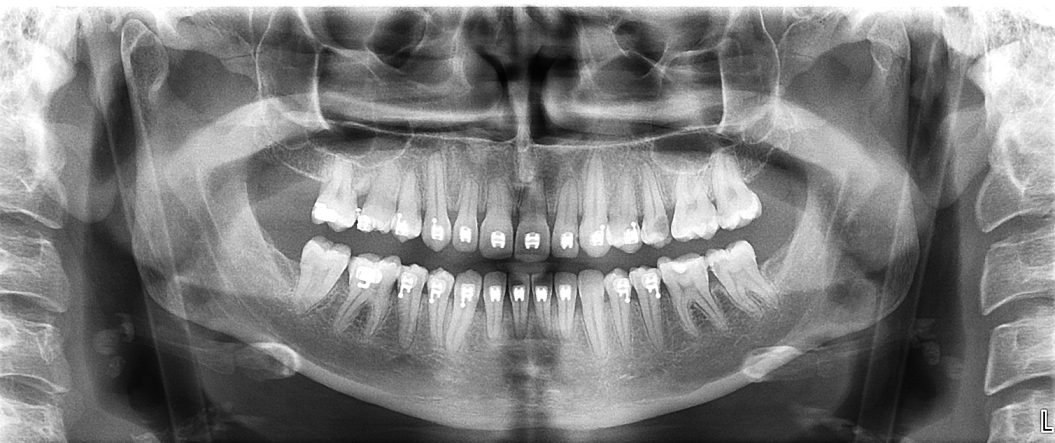

En este contexto, la tomografía computarizada de haz cónico (CBCT) se ha convertido en una herramienta esencial para los profesionales de la odontología. Gracias a la radiología 3D, los especialistas pueden evaluar con exactitud el volumen óseo disponible, identificar estructuras anatómicas importantes (como el nervio dentario o el seno maxilar) y diseñar el tratamiento con la máxima previsión y seguridad.

Para el paciente, esto se traduce en procedimientos más seguros, menos invasivos y con resultados más predecibles. En la fase de seguimiento, el CBCT también permite comprobar la correcta integración del injerto óseo y la evolución del tejido antes de colocar el implante definitivo.